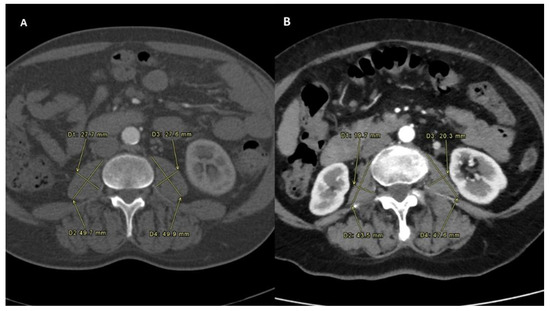

PMI was determined by measuring the major diameter and the minor diameter (measured perpendicularly to the major) of the right and of the left psoas on an axial CT scan at the time of TARE (Figure 1). A follow-up scan after TARE therapy for the assessment of PMI modification was performed at one, three and six months after the procedure (Figure 2) [14].

Figure 2. Sarcopenia status measured after the intra-arterial radioembolization in both the Sarcopenia group (A) and No-Sarcopenia group (B). All PMI measures were performed on the same level, which was between the third and the fourth lumbar vertebral body. To normalize the muscle mass for the patient’s height, this was divided by the square of the patients’ height. The PMI formula was PMI [mm/m2]: [(minor diameter of left psoas + major diameter of left psoas + minor diameter of right psoas + major diameter of right psoas)/4]/height in m2 [10].